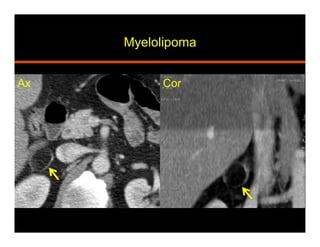

Myelolipoma

•  Benign and non functioning tumor

•  Mature adipose and hematopoeitic tissue

•  Heterogeneous, pseudo-capsule, calcifications

•  US: hyperechoic lesion

•  CT: macroscopic fat (HU<30)

•  MRI: T1 hyperintense signal suppresses with fat sat

India ink (chemical shift) artifact at myeloma-adrenal

interface and within the mass on out of phase

Ax Cor